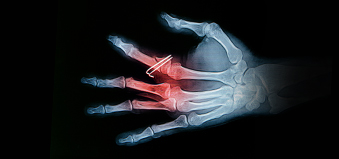

Hands are one of our most valuable tools. They’re also the most often-injured body parts. Hand injuries can be hard to treat, but most injuries are preventable with caution.

By far, the most vulnerable part on your body is your hands and fingers. Ironically, they are also one of the most important parts of your body. Without proper function of your hands and fingers, carrying out everyday tasks could be severely impaired. Keep your hands and fingers safe by doing the following: